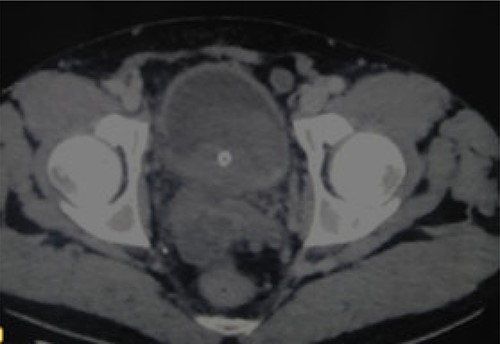

A 52-year-old man, diabetic, presented for gross hematuria associated with pelvic pain. His physical examination was normal. Ultrasonography and chest and abdominopelvic computed tomography (CT) scan revealed a urinary bladder tumor of 6×5 cm over the trigone and the left wall with left hydronephrosis (Fig. 1). Cystoscopic exploration revealed a solid lesion in the left wall and the trigone with a large base, infiltrating the left meatus. The patient underwent a complete transurethral resection of the bladder tumor. Histological examination showed a tumor proliferation made of nests and patches of large cells with eosinophilic cytoplasm and atypical and nucleated nuclei, infiltrating the bladder muscle. Tumor stroma is loaded with lymphoid elements (Fig. 2). The immunohistochemical study showed that this proliferation was negatively stained for (CK7 and CK20) but positively stained by epithelial markers (AE1/AE3). The final histopathological diagnosis was LELC (Fig. 3). A chest and abdominopelvic CT scan did not show pelvic lymphadenopathy or secondary location. Radical surgery was then decided without neoadjuvant therapy. Cystoprostatectomy with Bricker diversion and lymph node dissection was performed. The postoperative course was uneventful. The pathological examination of the surgical specimen confirms the diagnosis of a bladder LELC invading the perivesical fat. The patient was referred to the medical oncology department, where he received cisplatin-based chemotherapy. After 8 months of clinical and radiological check-ups, there was no functional complaint or any sign of reoccurrence.

CT revealing a bladder tumor of 6 × 5 cm over the trigone and left wall.